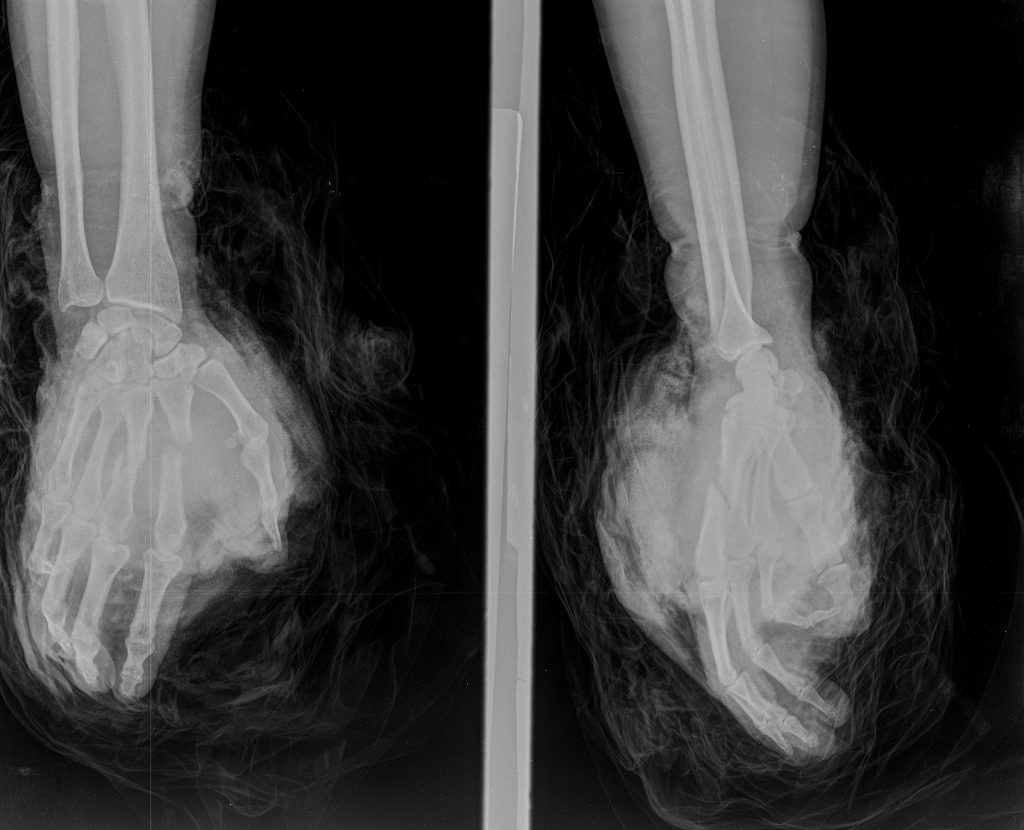

Ngày 24/10, Trung tâm Y tế Than Uyên đã phẫu thuật cấp cứu cho bệnh nhân nữ 43 tuổi, trú tại xã Mường Than, bị tai nạn lao động do máy thái chuối gây chấn thương phức tạp bàn tay phải. Sau hơn 3 giờ phẫu thuật, Ekip phẫu thuật đã tiến hành nối gân, nối thần kinh, mạch máu, kết hợp xương và khâu phục hồi vết thương, giúp bảo tồn bàn tay cho bệnh nhân. Hiện tại, sau phẫu thuật 4 ngày bàn tay bệnh nhân có cảm giác tốt, không có biểu hiện hoại tử. Ca mổ thành công thể hiện tinh thần trách nhiệm và kỹ năng chuyên môn vững vàng của đội ngũ y bác sĩ Trung tâm Y tế Than Uyên.